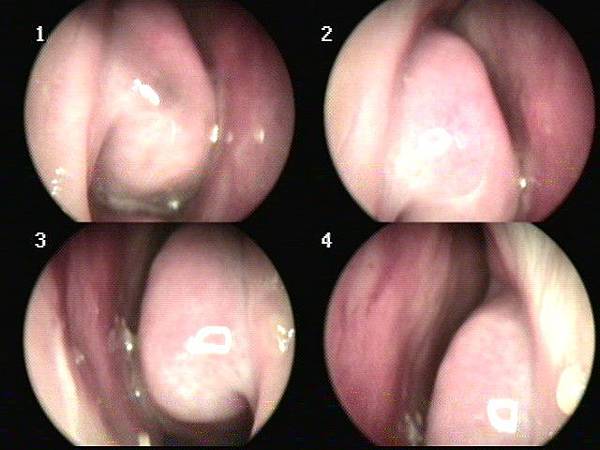

沒有好好治療的過敏性鼻炎

今天遇到的這位也是嚴重過敏性鼻炎的小朋友,

每天其實都有症狀,

但是卻懶得治療,